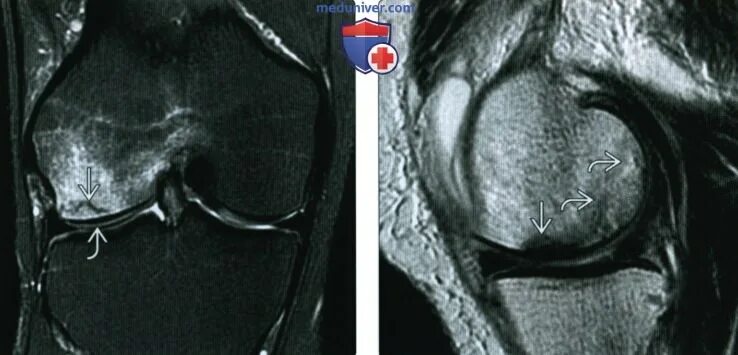

Перелом мрт или кт